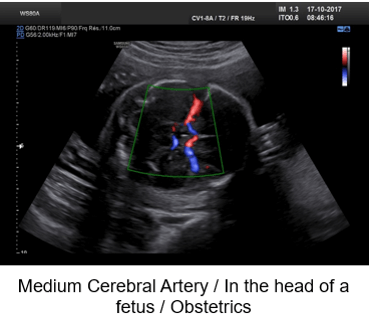

For example, pulsed Doppler is used in obstetrics to measure the flow of the umbilical and fetal arteries.

Examples of Images

Color Doppler is mostly used in fetal and hepatic ultrasound, where the primitive carotid and the hepatic vein are well visible.